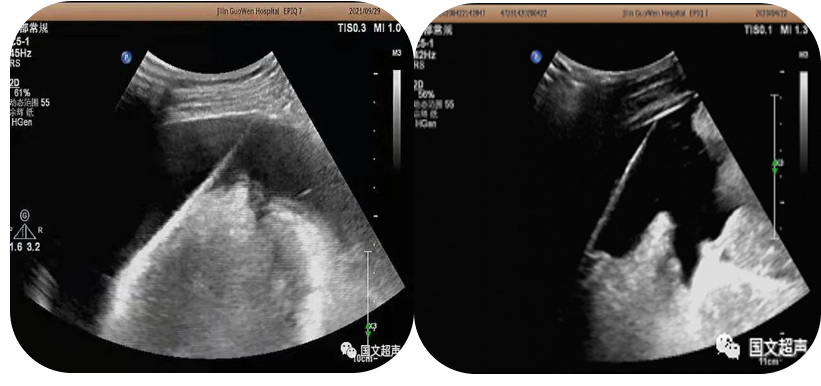

3.超聲引導(dǎo)下經(jīng)皮經(jīng)肝膽道置管引流、膽囊造瘺;經(jīng)皮腎造瘺、膀胱造瘺

超聲實(shí)時(shí)引導(dǎo)下將引流管放置在因腫瘤、結(jié)石等壓迫、堵塞梗阻擴(kuò)張的膽道、腎盂、膽囊、膀胱內(nèi)引流出潴留的膽汁、尿液,防止或緩解肝腎功能衰竭,進(jìn)而減緩患者痛苦為臨床爭(zhēng)取治療機(jī)會(huì)。

經(jīng)皮經(jīng)肝膽囊造瘺、膽道置管引流

經(jīng)皮腎造瘺

經(jīng)皮膀胱造瘺